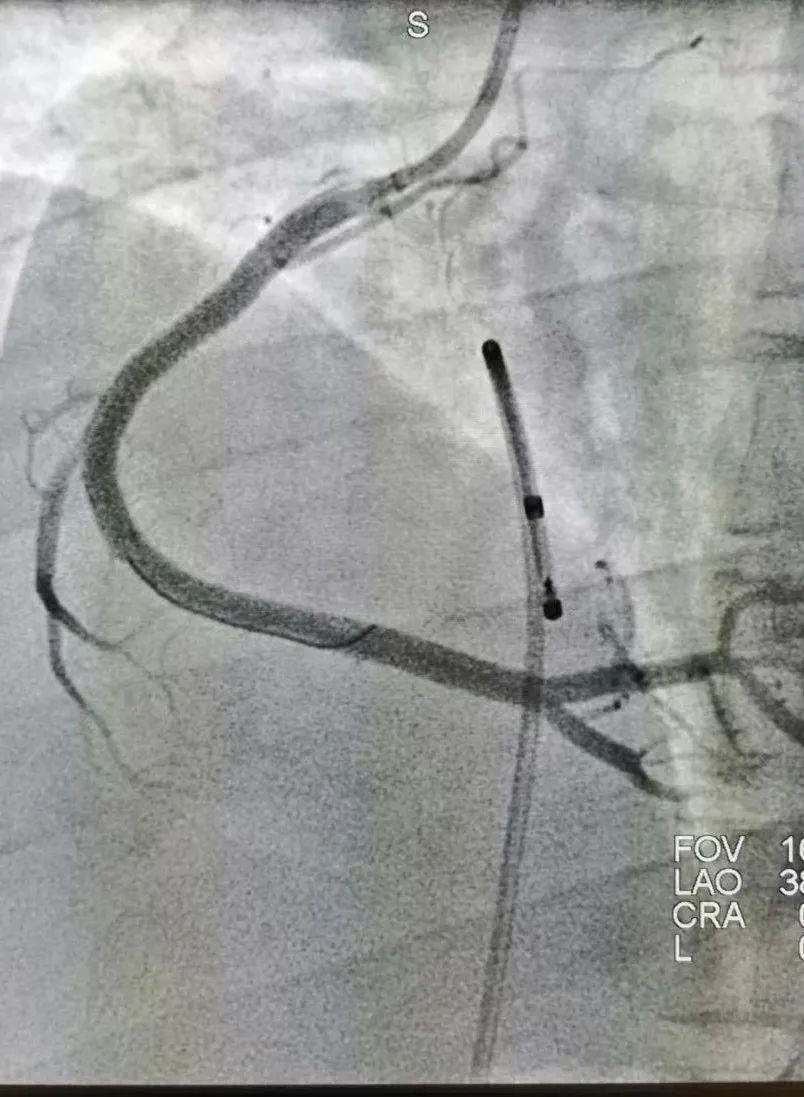

pci 术后影像

图片尺寸1440x1080